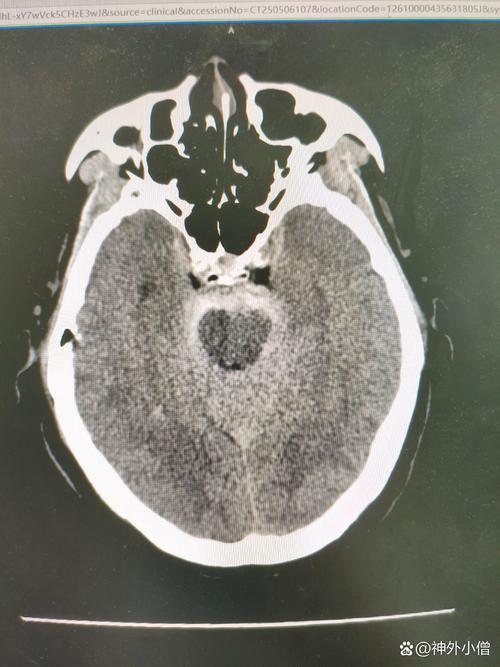

- 腔梗灶:这是“缺血性脑卒中”的一种特殊类型,全称是“腔隙性脑梗死”,它是由大脑深部的一些非常细小的动脉(穿通支)堵塞引起的,因为这些动脉很细,堵塞后坏死的脑组织范围也很小,形成一个像“小洞”或“小腔”一样的病灶,所以叫“腔隙性”梗死。

一句话总结: “脑内多发缺血及腔梗灶”意味着,在大脑的深部区域,存在多个由小血管堵塞或长期供血不足引起的小梗死灶。 它是脑小血管病的一种表现,通常与长期的高血压、糖尿病、高血脂等慢性病有关。